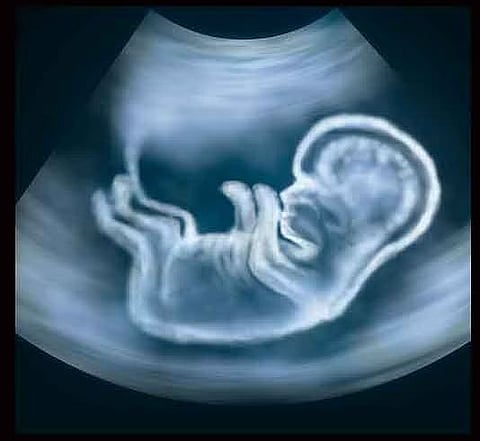

प्रसूतीपूर्व निदान तंत्राचा वापर करून बेकायदेशीररीत्या गर्भलिंग निदान करणे, गर्भपात करणे शिक्षेस पात्र आहे. मुलीचे प्रमाण मुलांच्या तुलनेत कमी होत असताना या सामाजिक समस्येकडे सर्वांनी गांभीयनि लक्ष देण्याचे आवाहन शासनातर्फे करण्यात आले आहे. नुकतेच छ. संभाजीनगर येथील बेकायदेशीर गर्भलिंग निदानाचे प्रकरण समोर आले. या पार्श्वभूमीवर तेथील जिल्हाधिकाऱ्यांना सतर्कतेचा इशारा देण्यात आला आहे.

सोनोग्राफी केंद्रात गर्भधारणापूर्व व प्रसूतीपूर्व निदान तंत्रे (लिंग निवडीस प्रतिबंध) कायदा १९९४ चे उल्लंघन होत असल्याचे आढळून आल्यास, तसेच असे कृत्य करण्याची जाहिरात करणा-यांची तक्रार आरोग्य विभागाच्या टोल फी. क्र. १८०० २३३ ४४७५ किंवा १०४ या क्रमांकावर नागरिकांनी नोंदवावी. या बाबीची खातरजमा करून संबंधित सोनोग्राफी केंद्रावर, व्यक्तीवर न्यायालयीन प्रकरण दाखल केले जाते, अशी माहिती अतिरिक्त संचालक डॉ. रेखा गायकवाड यांनी दिली